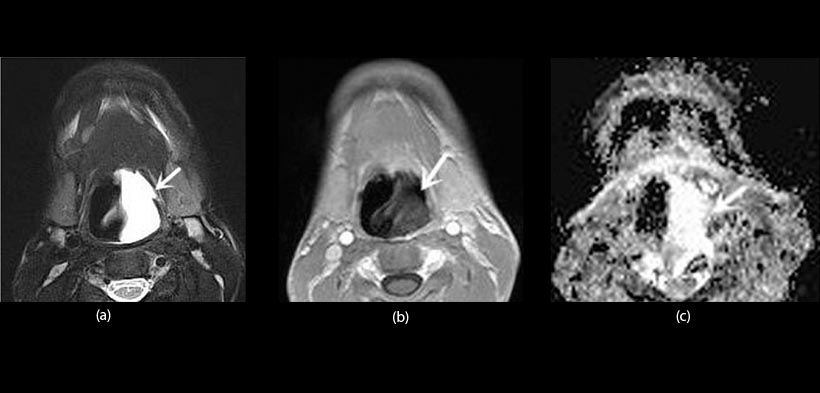

Fig. 3. Paciente varón de 17 años de edad con un quiste en la base de lengua. (a) vista axial en T2, imagen ponderada con supresión de grasa muestra una lesión hiperintensa homogénea (flecha) en la raíz de la lengua. (b) una mayor contraste de imagen de RM, vista axial en T1, imagen ponderada demuestra heterogéneamente realce periférico (flecha). (c) coeficiente de difusión aparente (ADC) revela una lesión hiperintensa (flecha). El valor ADC es 2.17x103mm2s-1.